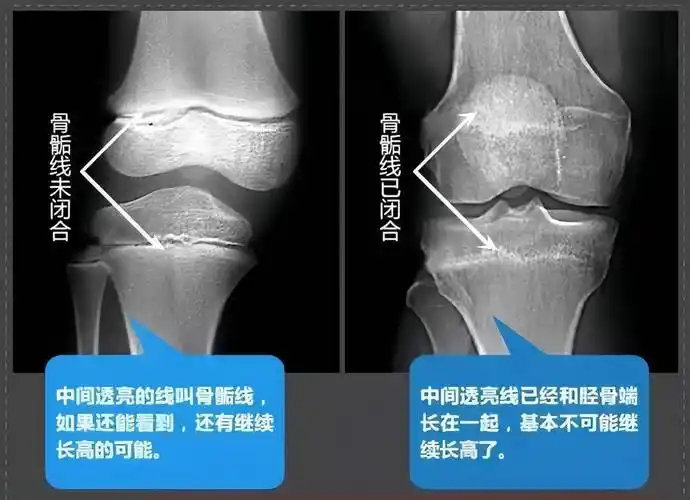

骨骺线,就是关节部位,骨骼末端的干骺端与骨骺之间的一条线,如果我们